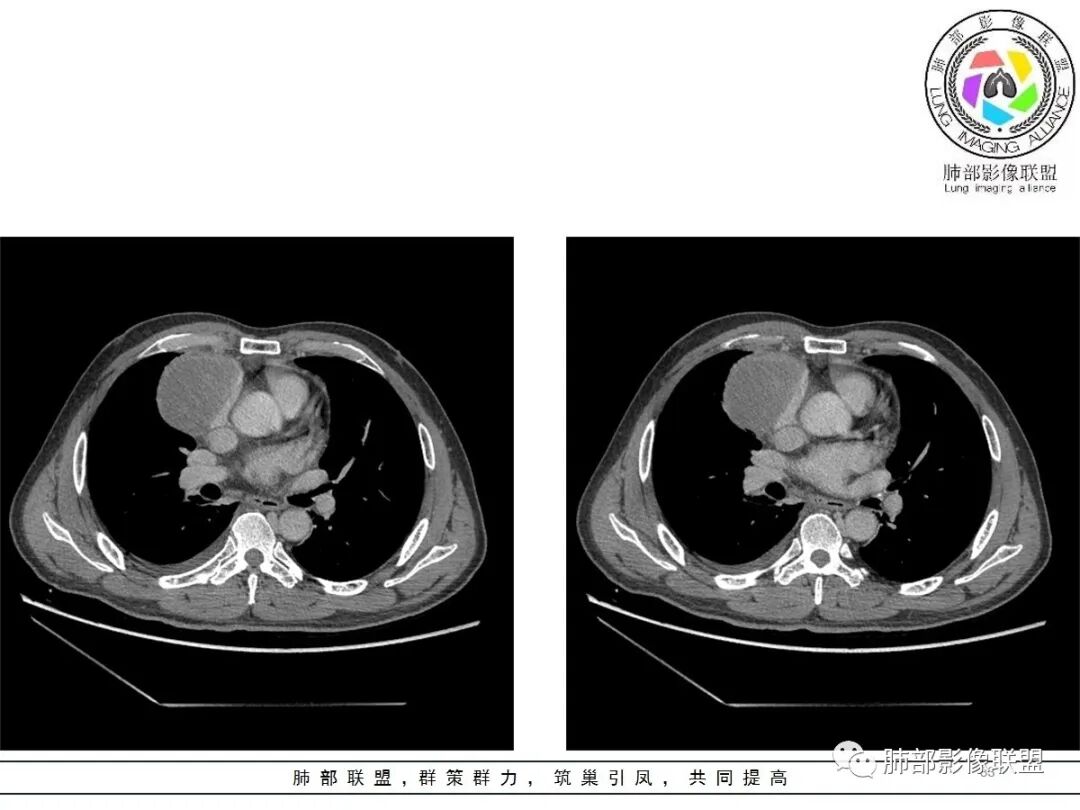

周围脂肪间隙密度增高,内部小点状很低密度影

右侧少量胸水

19日,4天后, 内部低密度影有,周围渗出增多,胸水增多

薄膜状强化

影像上周围病灶变化明显

常规肿瘤侵犯不支持,太快

应该是炎性病变渗出

脂肪密度明显,还有钙化、囊性病变,支持含脂质类病变破裂

周围是化学性炎症或出血所致

后期强化,可能与炎症有关

可能:1、肿瘤或瘤样病变破裂出血或内部物质外溢所致2、炎性病变所致

对比一下:

肿瘤样病变破裂所致纵隔炎应该没错

南边:肿瘤或肿瘤样病变破裂所致纵隔炎,这是大方向

结果:符合B型胸腺瘤伴出血,坏死囊性变,局部脓肿形成

1.老年男性  急性发病 胸痛1天

2.胸膜掀起,右侧内乳动脉略增粗,定位右前上纵隔内占位。

3.右上纵隔囊实性占位,边界清楚。中央见点状脂肪密度影,边缘见一点状钙化影,增强不均匀环形强化。

4.四天内病灶变化快,块影增大且不规则,包膜似不完整,边界不清,上份可见浸润或渗出,与周围心脏大血管及心包等间隙不清。胸水增多。

5.未见明显淋巴结增大

第一次的检查符合胸腺瘤影像学改变,短期内的形态学改变及突然出现的边界模糊或浸润等,符合出血或炎症。